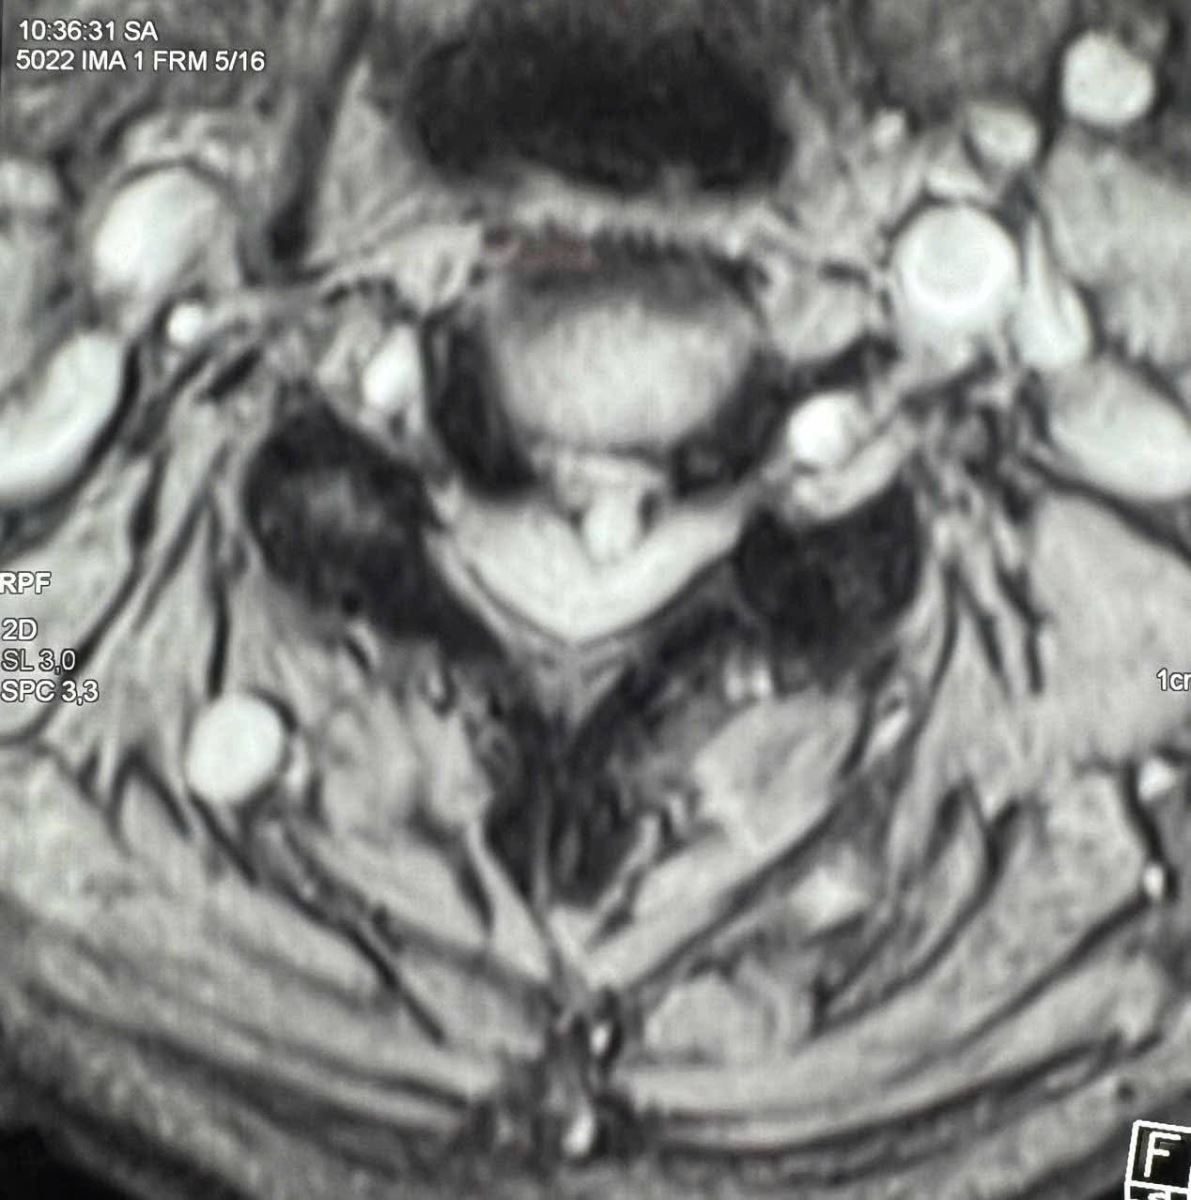

Qua thăm khám và chụp X-quang, MRI cột sống cổ, các bác sĩ xác định bệnh nhân bị thoát vị đĩa đệm C3–C4 thể trung tâm lệch trái, kèm phù tủy cổ, có nguy cơ tổn thương thần kinh tiến triển.

Bệnh nhân được phẫu thuật ACDF C3–C4 (lấy nhân đĩa đệm thoát vị, giải phóng chèn ép tủy – rễ thần kinh, hàn xương và cố định cột sống cổ lối trước).